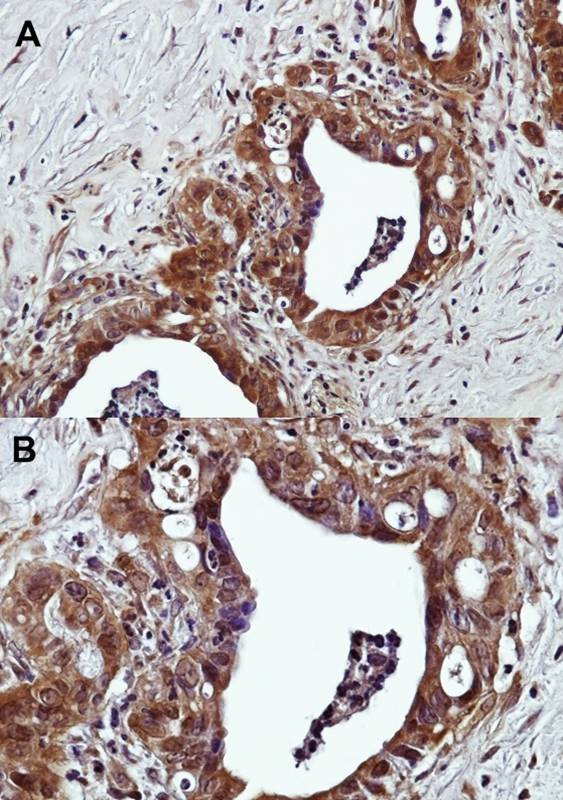

A:Immunohistochemical analysis of paraffin-embedded Human prostate adenocarcinoma, using GPR120 antibody at 1: 500 dilution.(20X). B:Immunohistochemical analysis of paraffin-embedded Human prostate adenocarcinoma, using GPR120 antibody at 1: 500 dilution.(40X)